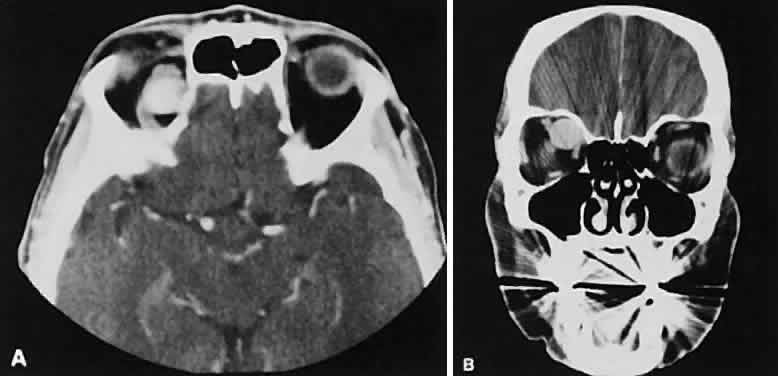

The muscle belly has a smooth contour with no edema of the adjacent orbital fat. We recently evaluated a patient with a referral diagnosis of Graves' orbitopathy. The patient was euthyroid but had severe orbital congestion typical of advanced Graves' orbitopathy. Imaging showed “dirty” orbital fat and lateral rectus muscle morphology that seemed atypical (Fig. 8). Biopsy specimen results showed a low-grade lymphoma. Hypertrophy of the medial rectus muscle can cause the medial wall to bow in toward the ethmoidal sinus from the chronic effects of pressure on the bone. The hypertrophied muscles also can give rise to a compressive optic neuropathy in the orbital apex as the enlarged muscles take their origin from the anulus of Zinn. Axial views of the apex show an apparent mass if the inferior rectus muscle is enlarged. It is imperative that additional views, sagittal or preferably coronal, be obtained to show the true nature of this apparent mass. Intracranial fat prolapse, seen by CT, may be another sign of optic neuropathy.44 An optic neuropathy also can be seen with relatively normal-sized EOM. An expanded fat compartment with optic nerve stretch has been associated with an optic neuropathy.45,46

Fig. 8. Low-grade lymphoma confined to orbit mistaken for Graves' ophthalmopathy in a 65-year-old man. A. On the axial view, orbital fat appears “dirty” with marked increase in soft tissue stranding. Muscles do not have a smooth appearance, lateral rectus muscles have lumpy appearance (arrow), and both lateral rectus muscles are disproportionately large for what typically is seen in Graves' orbitopathy. B. Coronal view also shows dirty orbital fat. Note left inferior rectus, which is small (arrowhead), and also is atypical in Graves' orbitopathy when there is enlargement of the other extraocular muscles.